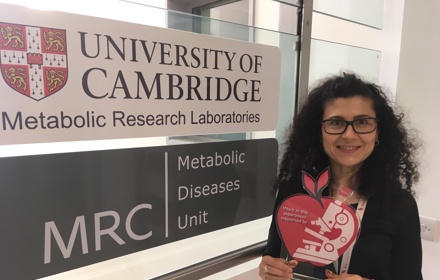

Celebrating careers in medical research

DRWF and the future of diabetes research